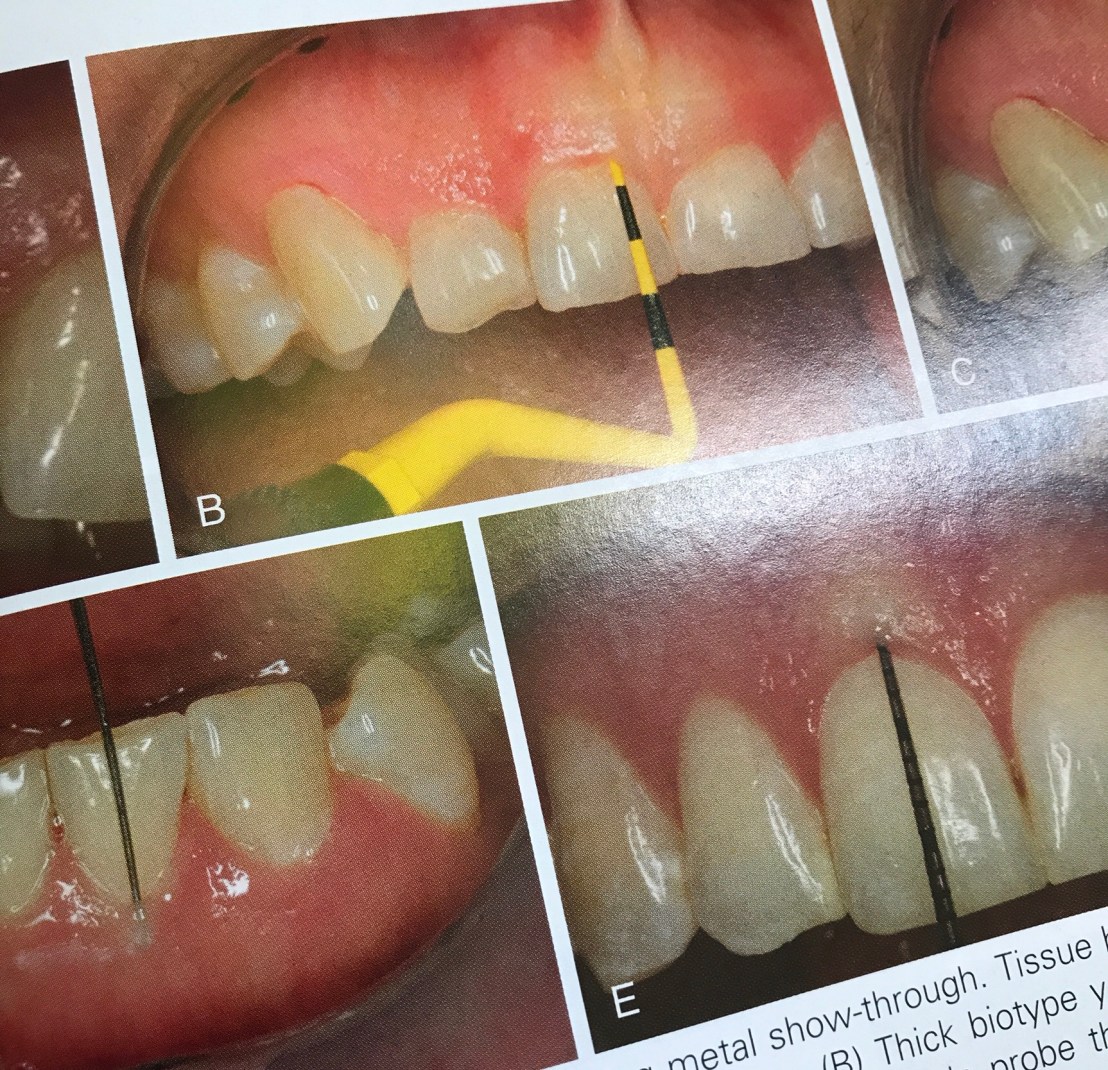

รูปแสดงการประเมินความโปร่งแสงของเหงือกโดยใช้การมองเห็นจากสีของ Probe ว่าจัดอยู่ใน Thick หรือ Thin biotype การนำไปใช้คือ ทำให้มองเห็นว่า Esthetic หลังทำว่า สอดคล้องกับความคาดหวังที่คนไข้มีอยู่หรือไม่?

การแก้ไขกรณีเหงือกเป็น Thin biotype คือทำ Subepithelial connective tissue grafting